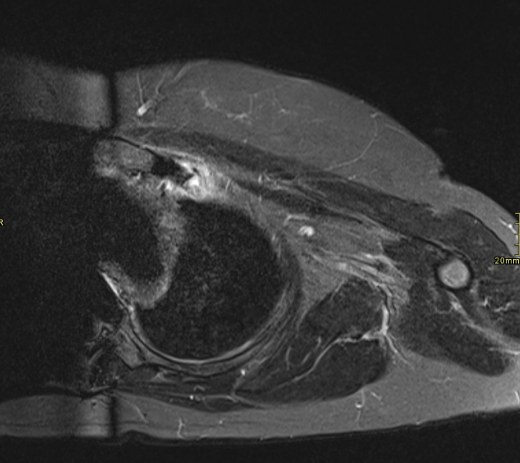

50 yr female was presented with neck and interscapular pain and was referred for MRI covering cervical spine and scapular region. On basis of findings on initial findings, patient was recalled for further MRI imaging.

What are the imaging findings and diagnosis?